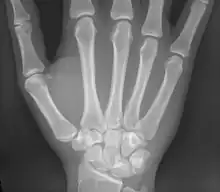

Les métacarpiens (ou os métacarpiens ou os du métacarpe) sont les os formant le métacarpe squelette de la paume de la main. Ils sont articulés dans leur partie supérieure[1] avec les os de la rangée distale du carpe et se prolonge au niveau de sa partie inférieure[1] par les phalanges proximales. Ces os sont unis par les muscles interosseux.

Les métacarpiens sont cinq petits os longs numérotés de 1 à 5, de dehors en dedans en position anatomique : 1 correspond au pouce et 5 à l'auriculaire. Chacun se compose d'une base proximale, d'un corps et d'une tête distale.

Les métacarpiens ont deux points d'ossification : un primaire dans la diaphyse pour la base et le corps et un secondaire dans la tête.

Pour le premier métacarpien, le point d'ossification secondaire est dans la base.

Os humain de la main